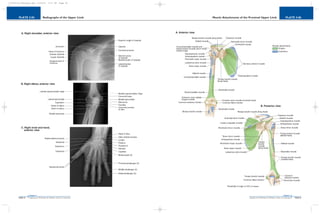

PLATE 2-06

Muscle Attachments of the Proximal Upper Limb

PAGE 34

PLATE 2-05

Radiographs of the Upper Limb